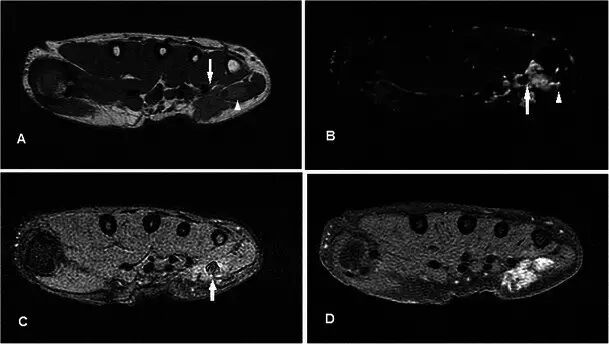

腱鞘巨细胞瘤Giant cell tumour of tendon sheath GCTTS是常见的肿瘤,通常在30-50岁时表现为无痛的肿块,具有轻微的女性偏好。 它们通常存在于与退行性关节相关的手或脚中,并且被认为是对邻近炎症的反应性损伤而不是真正的肿瘤[40]。 GCTTS在组织学上是良性的,但是在10-20%的病例中,在平片上可以看到相邻骨的压力变化[41](图13a)。MR显示与关节和腱紧密相关的损伤,主要是T1w序列上的低信号和T2w序列上的中等至稍高的信号(图13b-e)。 GRE序列上可见典型的异常图像,因为血铁素沉积,这是一个有用的特点[42]。 由于在胶原基质中存在许多增殖性毛细血管,观察到强的增强。 鉴别诊断包括局灶性结节性滑膜炎,其还含有铁氧化物,而更加异质的信号和增强可导致与软组织肉瘤的混淆。

图13.GCTTS在一名23岁的女性,有1年的右拇指肿胀和轻度疼痛的病史。 (a)平片显示在第一掌骨(箭头)的头部的明确的透亮区。 (b)T1w序列显示包围屈肌腱长肌的中间信号的分叶皮下病变(箭头)。 (c)病灶在T2w-FS序列上显示不均匀高信号。 在下面的骨头上有压力侵蚀。 (d)在GRE序列(箭头)上证明了易感性的Foci。 (e)有积极和相当均匀的增强